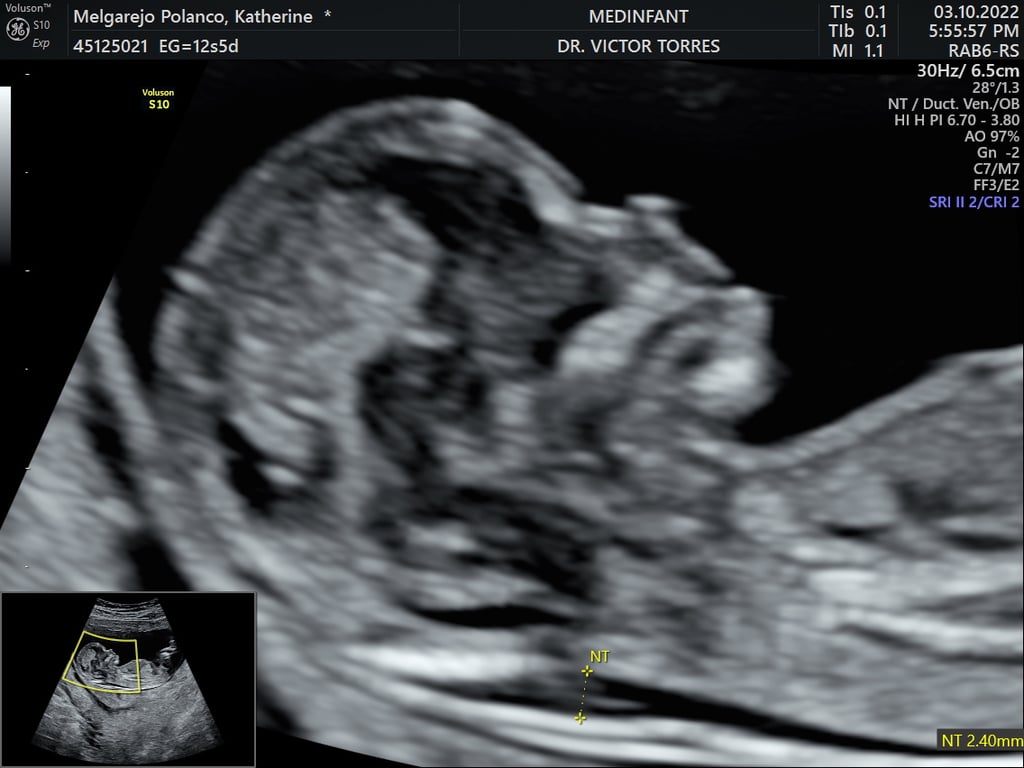

ecografía morfológica primer trimestre (genética y más)

12 - 14 semanas